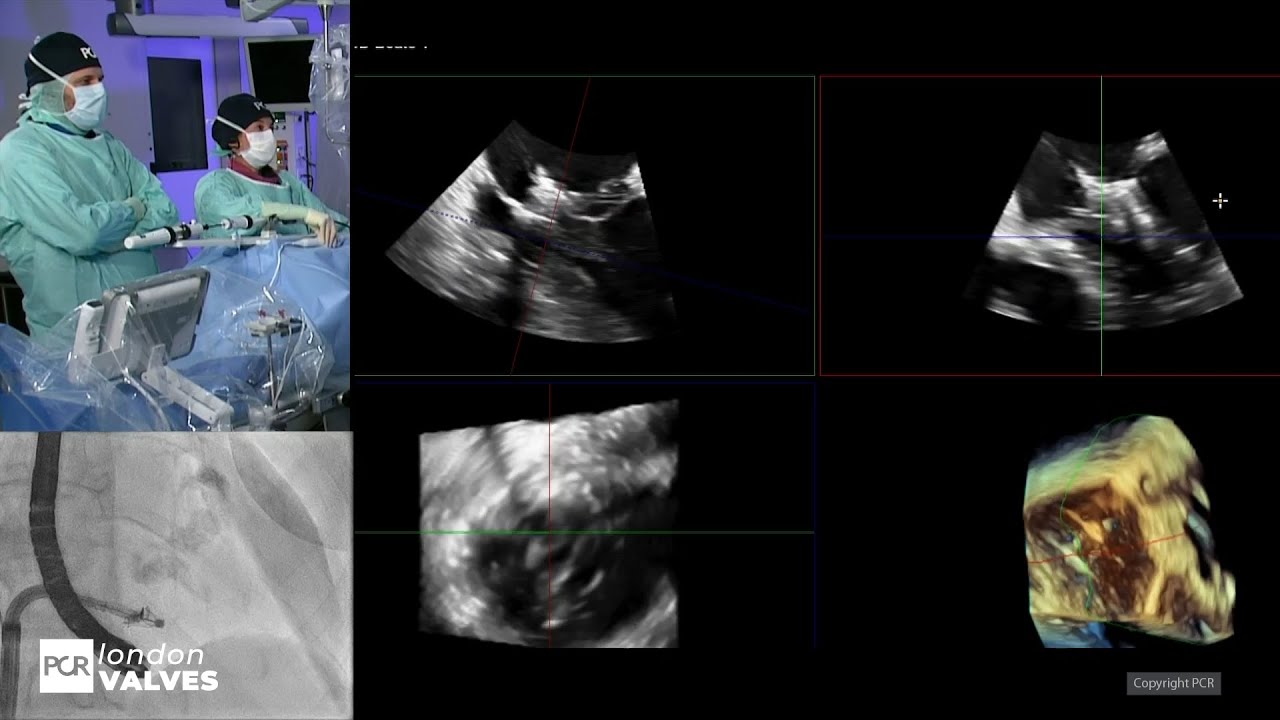

Transcatheter tricuspid valve repair: LIVE Educational Case from University Medical Center - Mainz, Germany